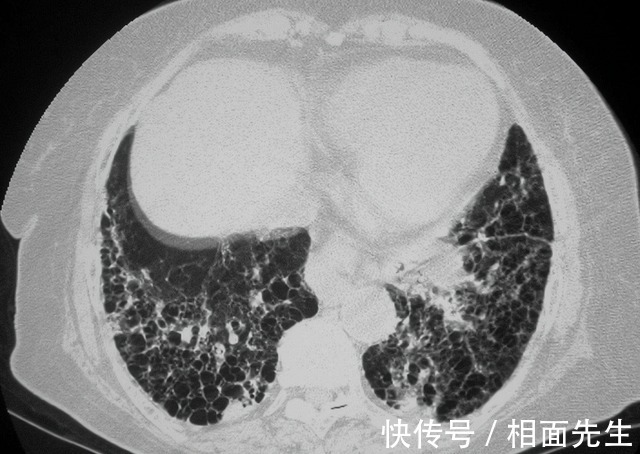

但是到底是什么中毒一直没能确认,直到12月17号,检测结果终于出来了,显示是百草枯中毒,一家人吓傻了,农村人都知道百草枯中毒意味着什么,家人以为是萌萌高三学习压力大,想不开自己喝下的毒药。

一开始,陈某还不承认是自己下毒谋害小姨子,直到看瞒不过去才承认是自己下毒,但却没有透露作案动机,萌萌的姐姐说,自己和丈夫没有任何矛盾,自己也不知道丈夫为何如此狠心,从6号投毒到17号检测出百草枯,陈某一直没承认过,让萌萌错过了最佳治疗时间。